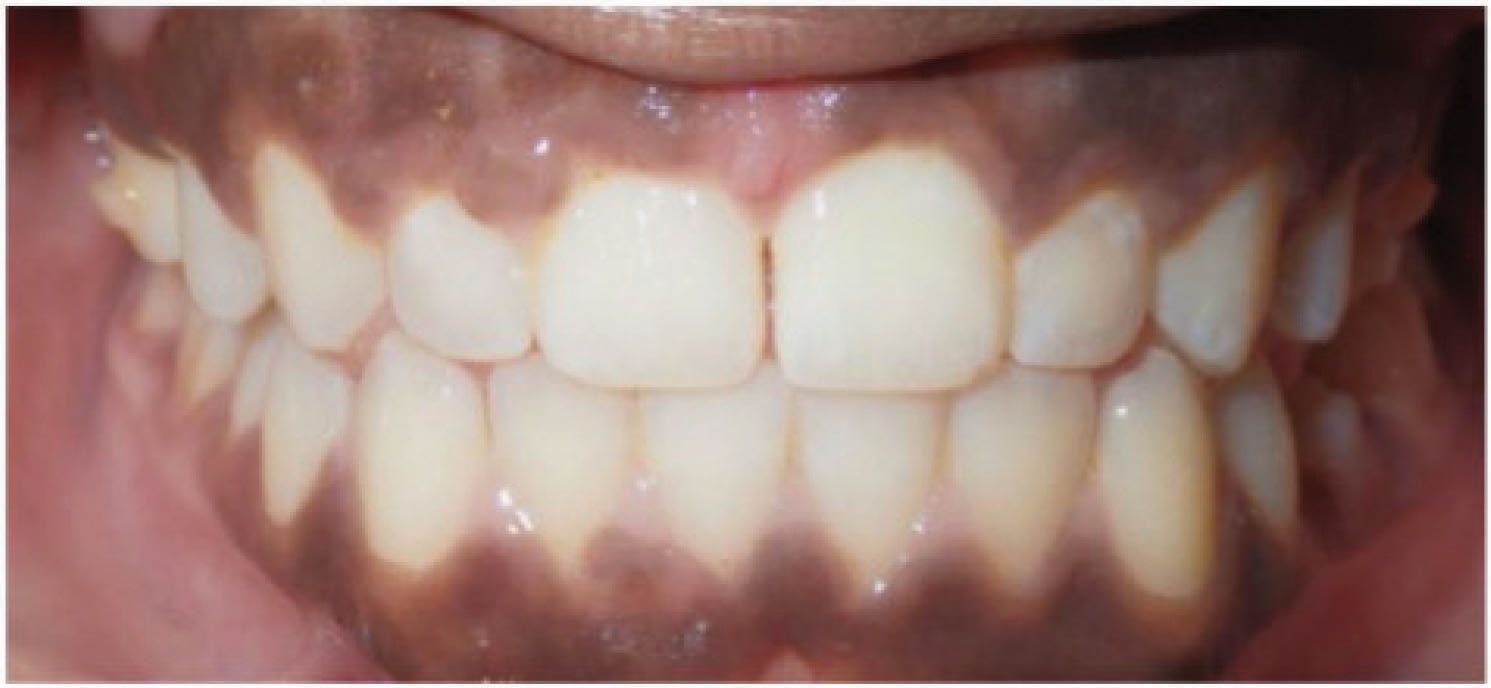

در بیماری که در شکل 38-6 مشاهده میکنید، یعنی بیماری که سانترالهای بالا او از هم به صورت تیپینگ دور شدهاند، درمان با الاینر خیلی عالی میشود، و تصویر آخر نرم افزار به نتیجه درمان خیلی شبیه میشود (شکل 39-6 و 40-6).

شکل 39-6